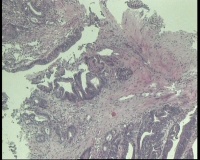

性别

女

年龄

43岁

临床诊断

结肠CA

一般病史

进镜达横结肠近肝曲,见不规则增生性肿物,环周生长,表面充血糜烂,触之易出血,肠腔狭窄,镜身无法通过

标本名称

肠镜活检

大体所见

肠镜活检4块

镜下腺体异型小,纤维间质反应,能直接报结肠腺癌吗?

可一类报告报:管状绒毛状腺癌

高-中分化腺癌。